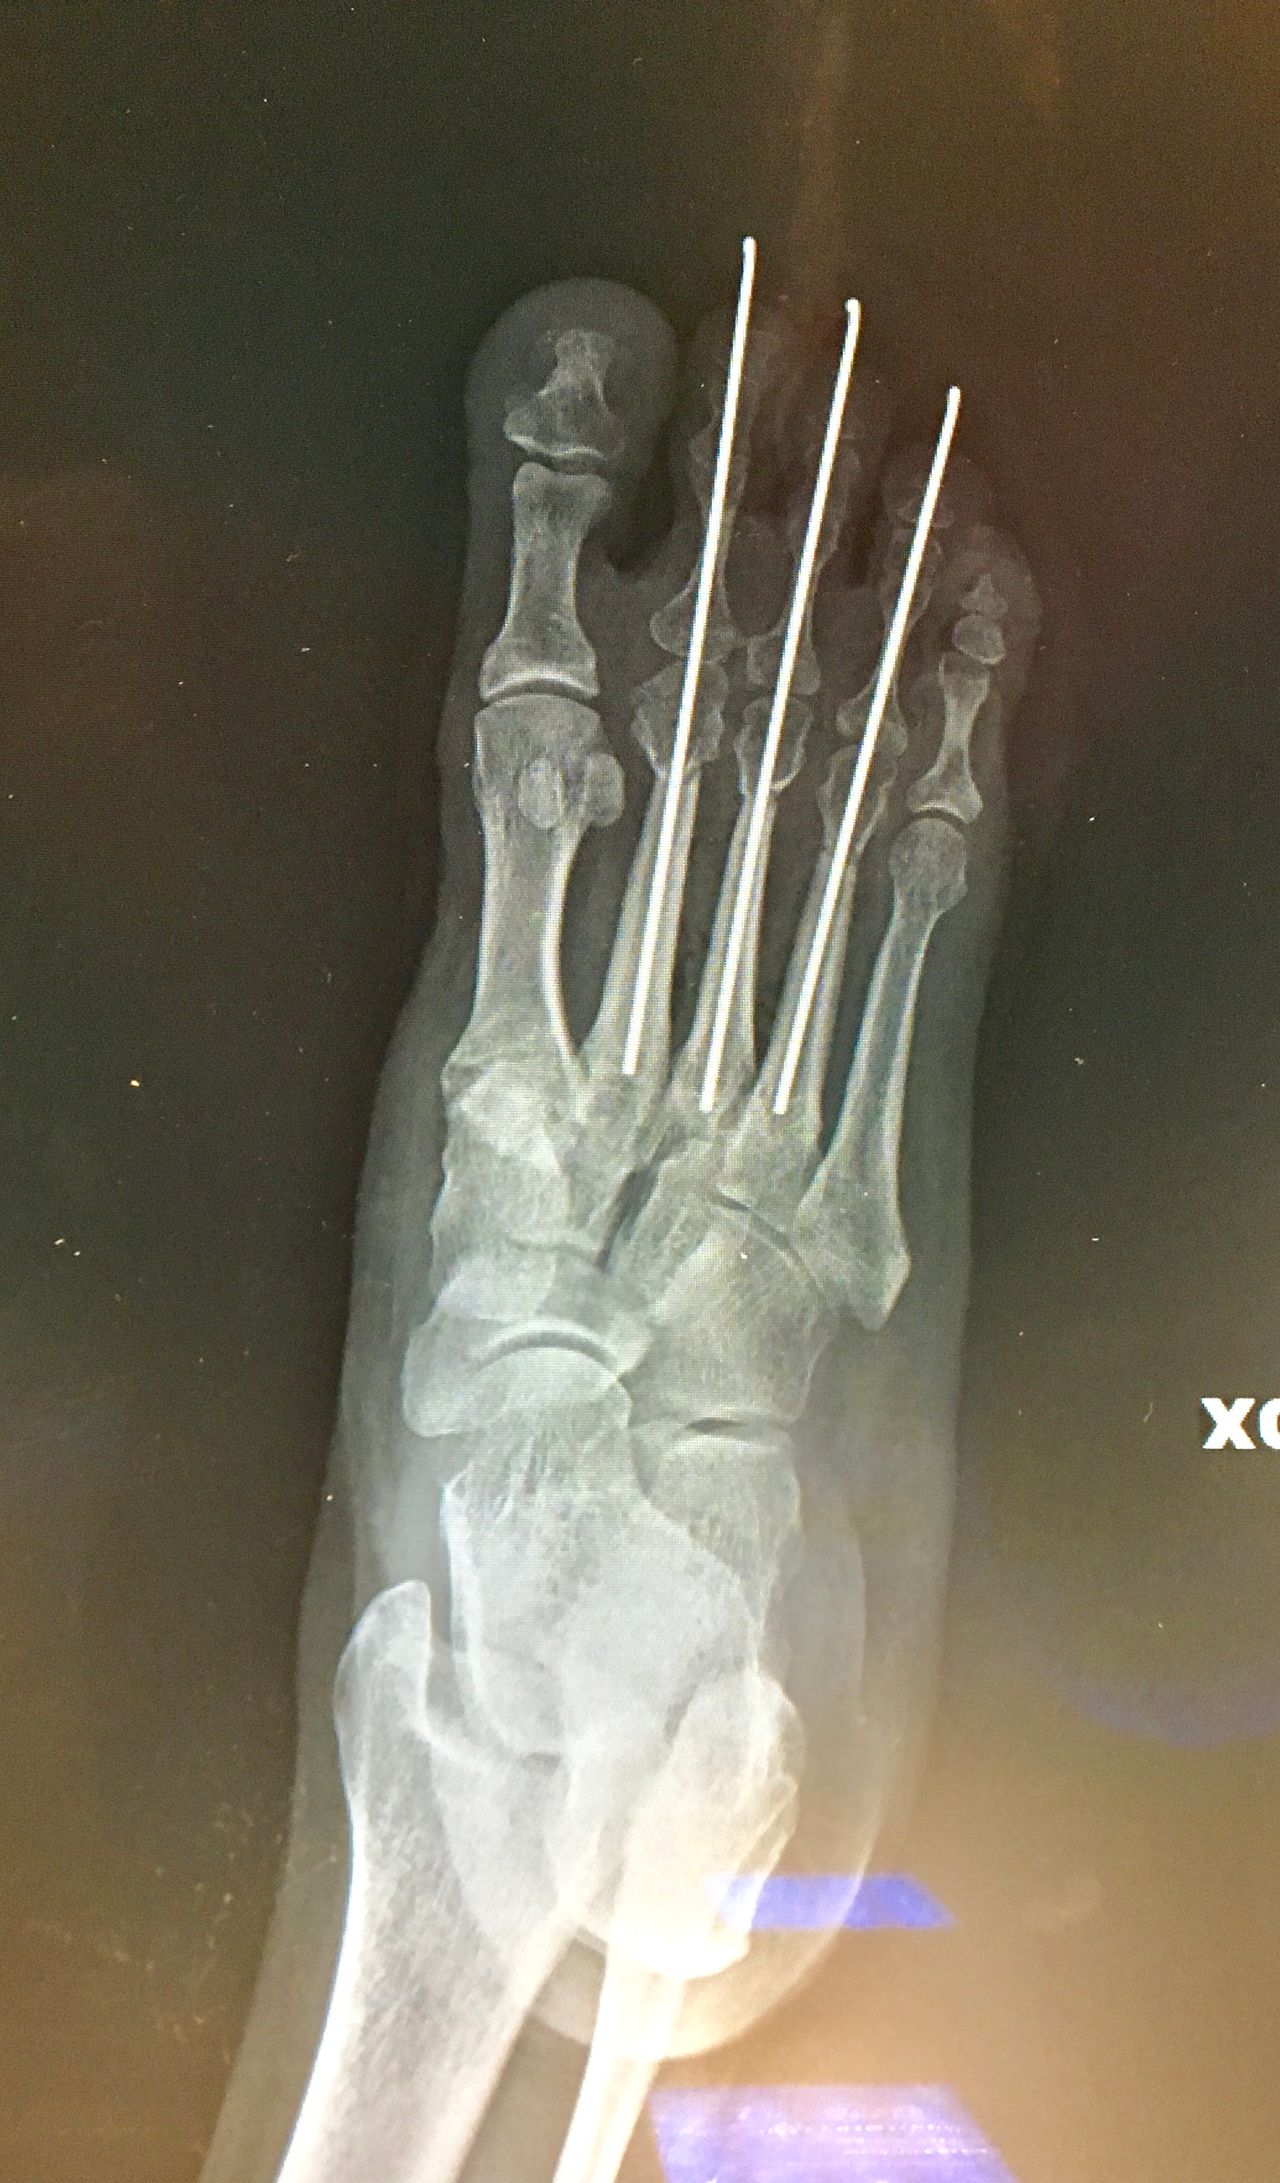

La chirurgia del piede

Alluce valgo

• Chirurgia del piede